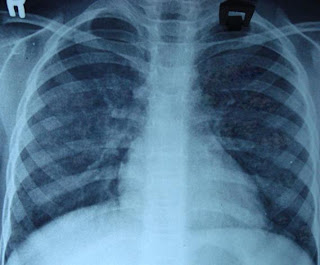

Hemosiderosis Pulmoner Idiopatik (adanya zat besi di dalam paru-paru) adalah penyakit yang jarang terjadi tetapi sering berakibat fatal, dimana darah dari kapiler masuk ke dalam paru-paru.

DIAGNOSA

Diagnosis ditegakkan berdasarkan gejalanya.